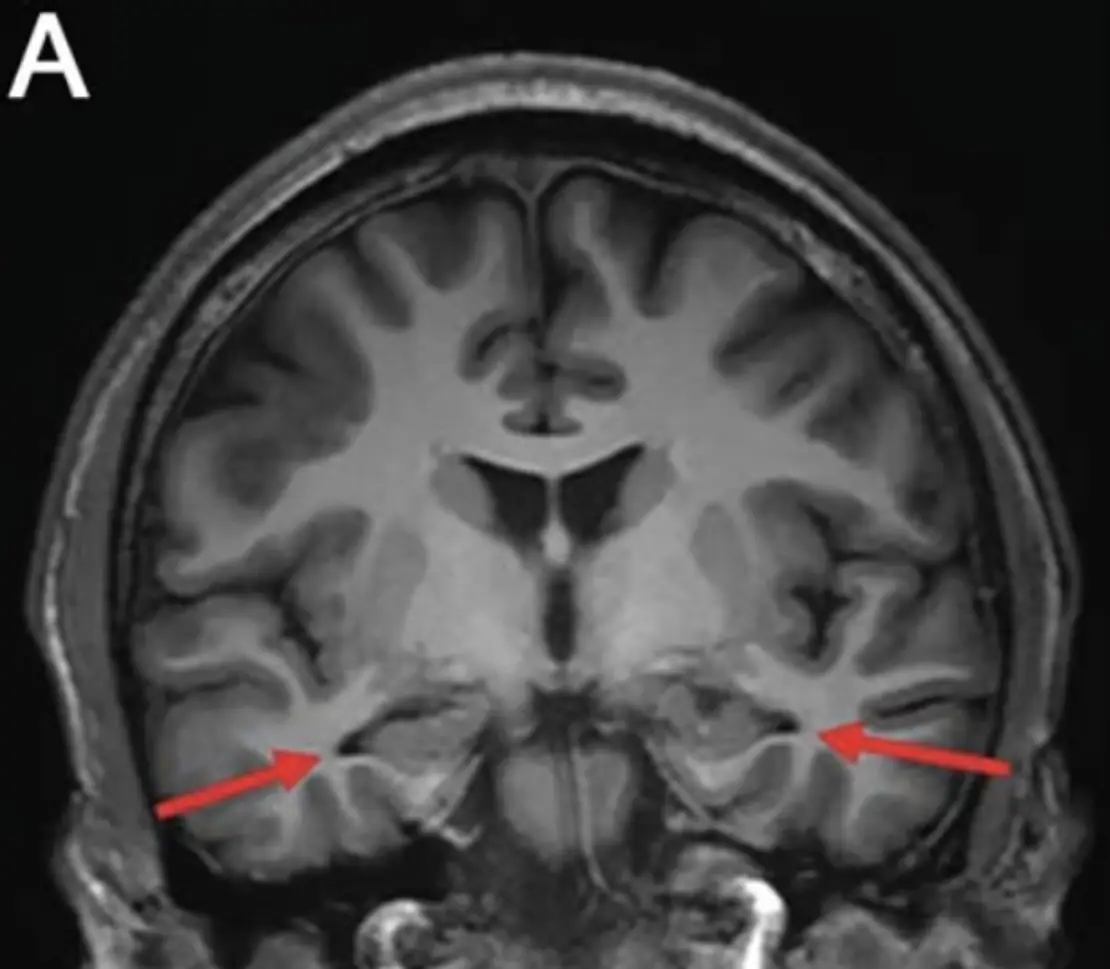

Brain scans carried out in 2022 then confirmed doctors fears that the lad had early-onset Alzheimer's, as they revealed the impact that the devastating disease had upon his brain.

The MRI results showed that his hippocampus - which is the part of your brain responsible for long and short-term memory as well as learning - had shrunk significantly.

On top of this, the 19-year-old's parietal and temporal cortices that are in charge of critical thinking had also visibly reduced in size.